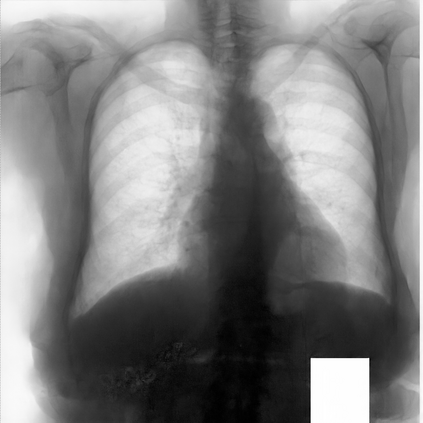

Multi-organ segmentation of X-ray images is of fundamental importance for computer aided diagnosis systems. However, the most advanced semantic segmentation methods rely on deep learning and require a huge amount of labeled images, which are rarely available due to both the high cost of human resources and the time required for labeling. In this paper, we present a novel multi-stage generation algorithm based on Generative Adversarial Networks (GANs) that can produce synthetic images along with their semantic labels and can be used for data augmentation. The main feature of the method is that, unlike other approaches, generation occurs in several stages, which simplifies the procedure and allows it to be used on very small datasets. The method has been evaluated on the segmentation of chest radiographic images, showing promising results. The multistage approach achieves state-of-the-art and, when very few images are used to train the GANs, outperforms the corresponding single-stage approach.